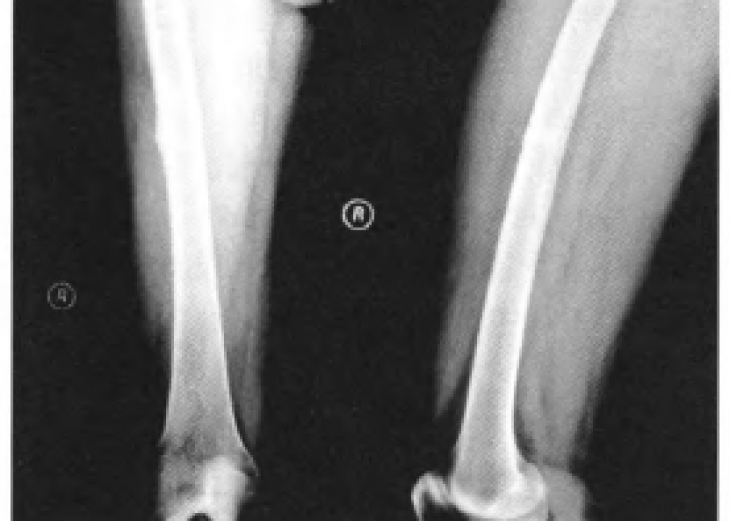

骨软骨瘤是一种发生在骨表面,顶端有软骨帽覆盖的良性骨肿瘤。大多发生在长管状骨的干骺端,约占骨肿瘤的9.3%,占骨良性肿瘤的36%左右。然而,发生在脊柱的骨软骨瘤在临床上较为罕见。除此之外,...